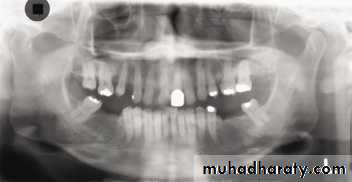

A dental panoramic tomograph showing the main anatomical ghost or artefactual shadows drawn in on one side of the radiograph, PI — palate, Md — mandible, CV — cervical vertebrae.